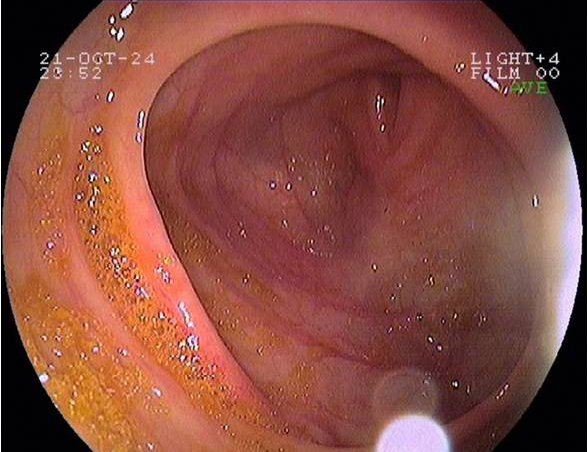

Imágenes tomadas durante la endoscopia digestiva alta y la colonoscopia. Se aprecia una mucosa de aspecto y vascularización normal, sin lesiones visibles. Se progresa con el colonoscopio hasta el íleon. Todo resulta macroscópicamente normal. Se toman biopsias de todos los segmentos explorados.

Pruebas complementarias: panendoscopia oral y colonoscopia

La endoscopia es el método de elección para el diagnóstico y seguimiento de la EII. Permite una visión macroscópica de la mucosa intestinal y la toma de múltiples biopsias para el estudio histológico.

En todos los pacientes en los que se sospeche una EII está indicada la realización de una colonoscopia completa con ileoscopia y una endoscopia digestiva alta.

Es la técnica de elección para diferenciar entre colitis ulcerosa (CU) y enfermedad de Crohn (EC), así como para localizar y valorar la extensión de la enfermedad.

Realizamos una endoscopia digestiva alta y una colonoscopia a la paciente con toma de biopsias, obteniendo el informe de Anatomía patológica.